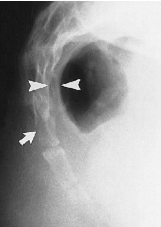

Q what is the name of this measurement? and what is the average + range?

A: Atlantodental Interspace (ADI)

assesses the integrity of the transverse ligament. Average and range for Adults: 1-3 mm. Average and range for Children: 1-5 mm